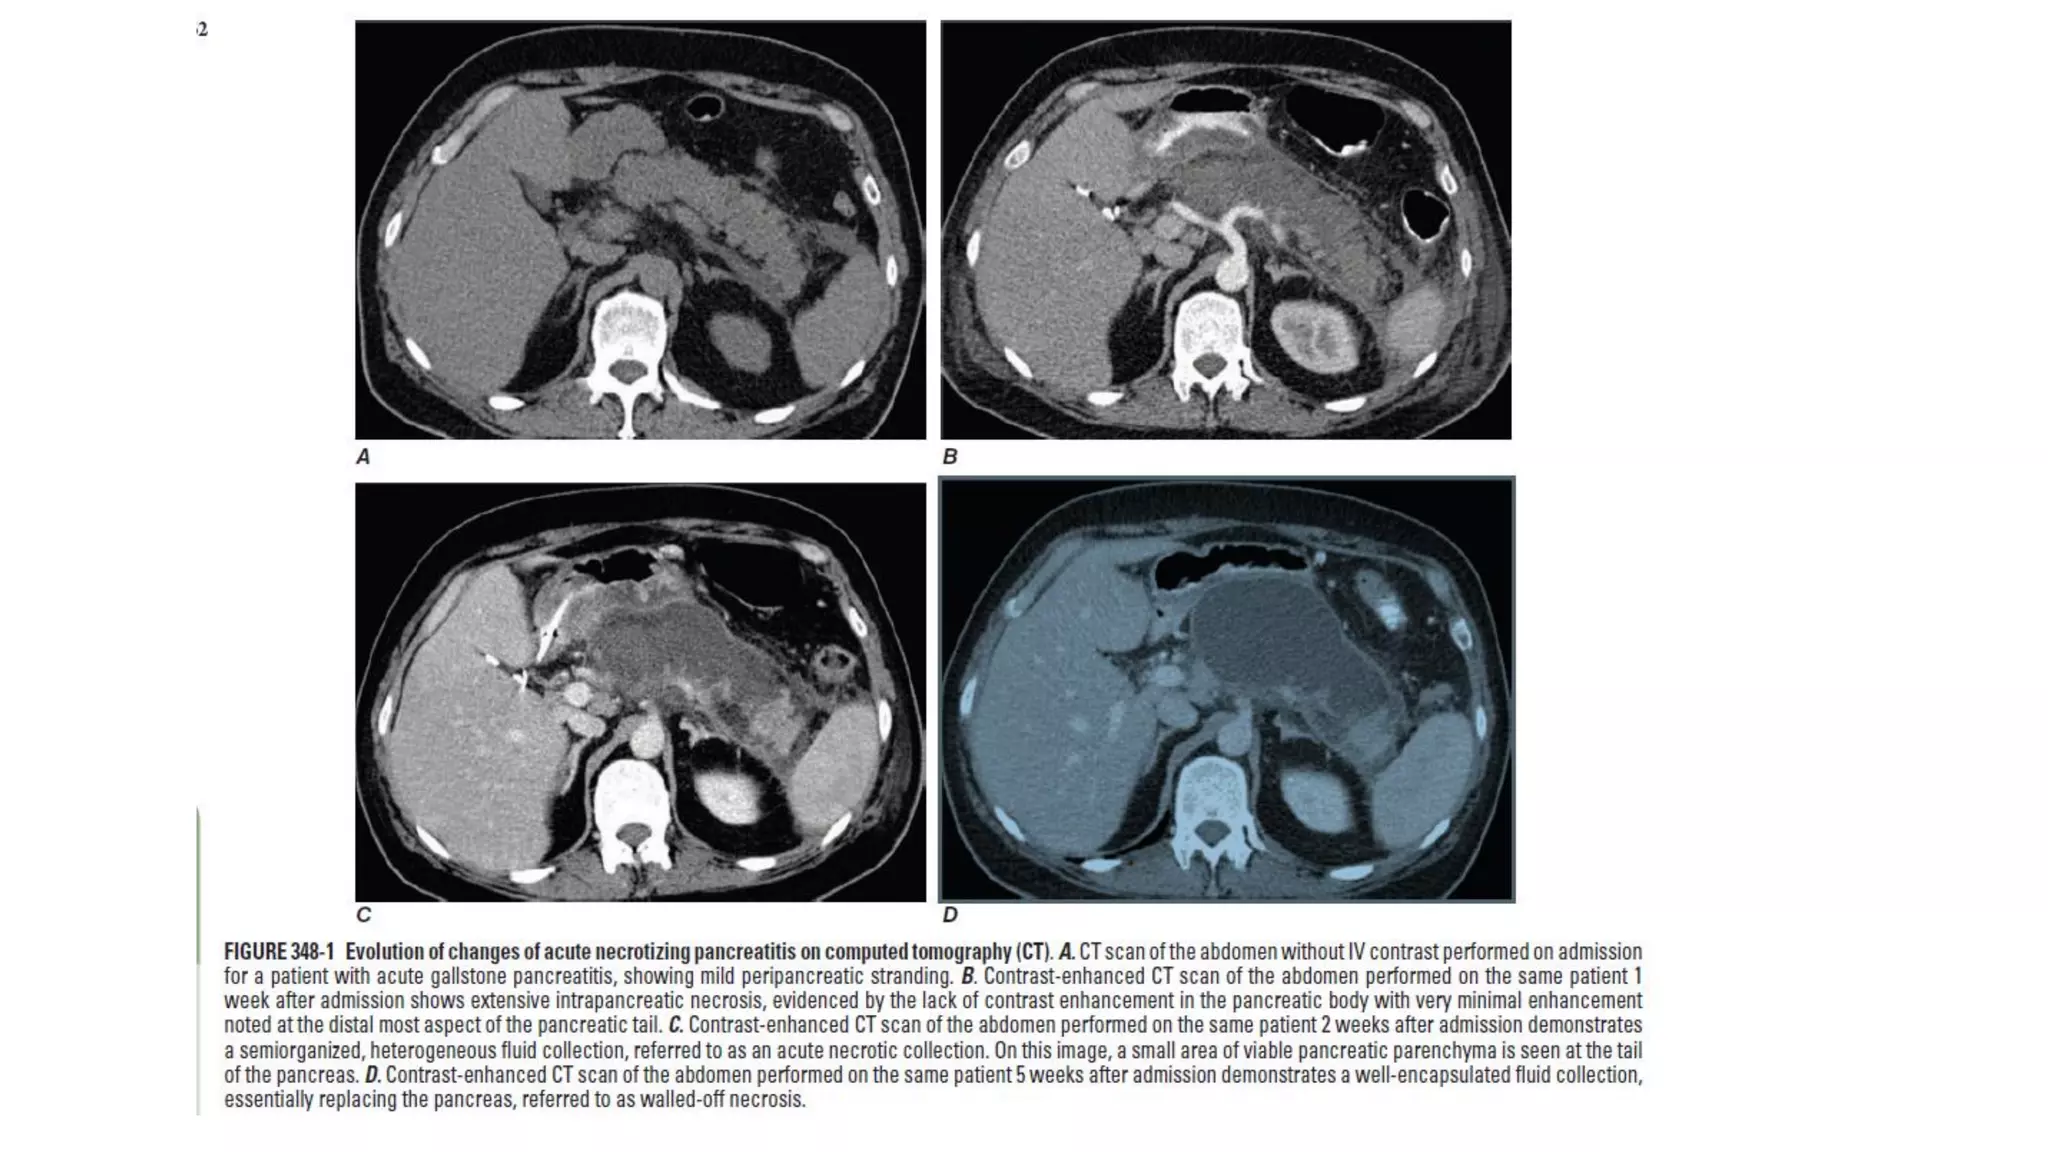

CT scan of the abdomen without IV contrast performed on admission

for a patient with acute gallstone pancreatitis, showing mild peripancreatic

stranding.

Contrast-enhancedCT scan of the abdomen performed on the same patient1 week after admission shows

extensive intrapancreaticnecrosis, evidenced by the lack of contrast enhancement in the pancreaticbody with

very minimal enhancement noted at the distalmost aspect of the pancreatictail.

Contrast-enhanced CT scan of the abdomen performed on the same patient 2 weeks after

admissiondemonstrates a semiorganized, heterogeneous fluid collection, referred to as an acute

necrotic collection. On this image, a small area of viable pancreatic parenchyma is seen at the tail

of the pancreas

Contrast-enhanced CT scan of the abdomen performed on the same patient 5

weeks after admission demonstrates a well-encapsulated fluid collection,

essentially replacing the pancreas, referred to as walled-off necrosis.

CT scan ofthe abdomen without IV contrast performed on admission for a patient with acute gallstone pancreatitis, showing mild peripancreatic stranding.

Contrast-enhancedCT scan ofthe abdomen performed on the same patient1 week after admission shows extensive intrapancreaticnecrosis, evidenced by the lack of contrast enhancement in the pancreaticbody with very minimal enhancement noted at the distalmost aspect of the pancreatictail.

Contrast-enhanced CT scanof the abdomen performed on the same patient 2 weeks after admissiondemonstrates a semiorganized, heterogeneous fluid collection, referred to as an acute necrotic collection. On this image, a small area of viable pancreatic parenchyma is seen at the tail of the pancreas

Contrast-enhanced CT scanof the abdomen performed on the same patient 5 weeks after admission demonstrates a well-encapsulated fluid collection, essentially replacing the pancreas, referred to as walled-off necrosis.